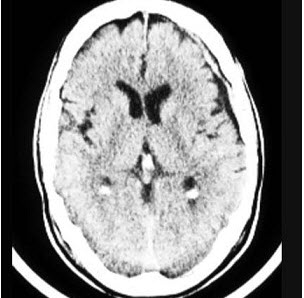

患者,女,65岁,进行性加重的近记忆力减退,缓慢行走,交谈能力减退,付错钱。CT表现如图

(单选题)最可能的诊断是( )

A:A1zheimer病

B:帕金森病

C:抑郁症

D:轻度认知障碍

E:多发性脑梗死

A:CT和MRI检查常显示脑皮质萎缩及侧脑室扩张